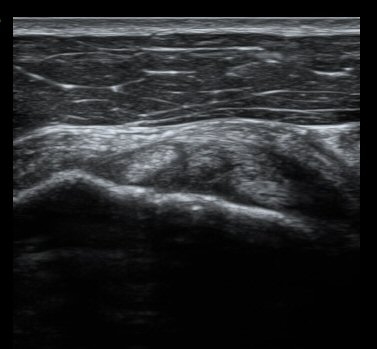

±Ø»ó°Ç Á¾´Ü¸é°Ë»ç¿Í Ⱦ´Ü¸é°Ë»ç¿¡¼­ ±Ø»ó°Ç³» ¹Ì¼¼ÇÑ °£±ØÀÌ °üÂûµÊ(±×¸² 6, 7, 8).